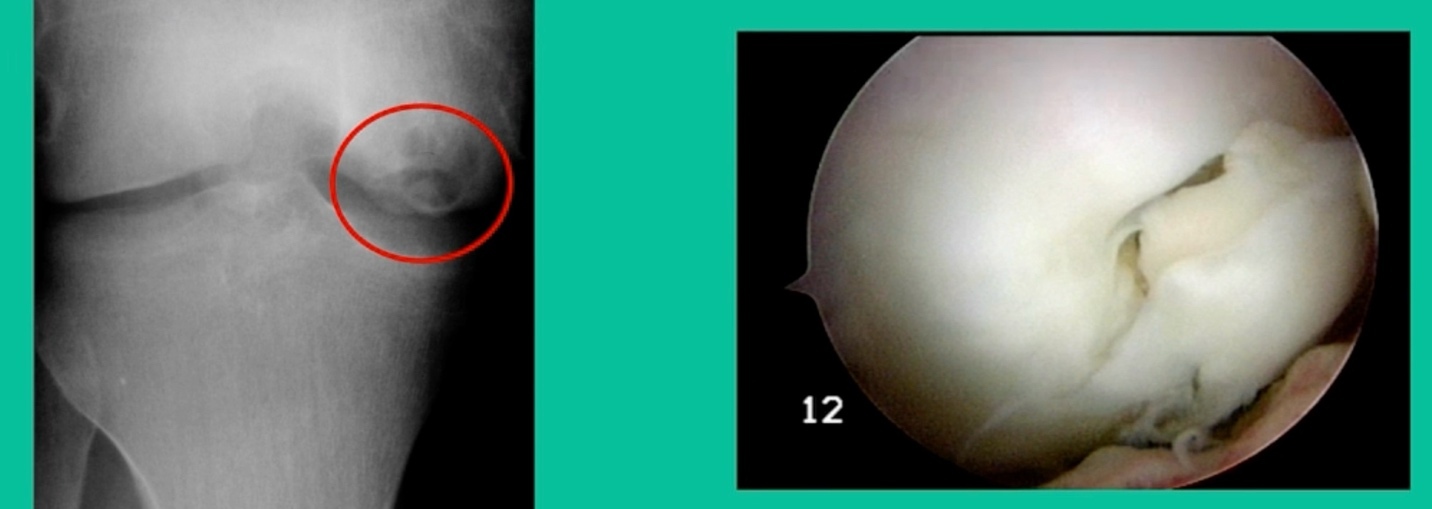

43-Year-Old, symptomatic medial femoral condyle.

D1 football player formally, affecting ADLs. For this one, I initially just wanted to watch it. This looks pretty small when he came in. Let’s see what happens. Six months later, this is where he progressed to.

We get in there, it’s delaminated, not much bone, nothing to fix in my mind, and so we drilled it.

How do these do? There’s actually reasonable data for marrow stimulation for OCD. But if you have the option for small defects, I would prefer an osteochondral allograft over microfracture based on the literature. That’s the take-home. Marrow stimulation, if you do it, you’re probably better off drilling it. We showed that we could reduce revision rates with marrow stimulation by two-thirds if you drill it versus use a microfracture awl.